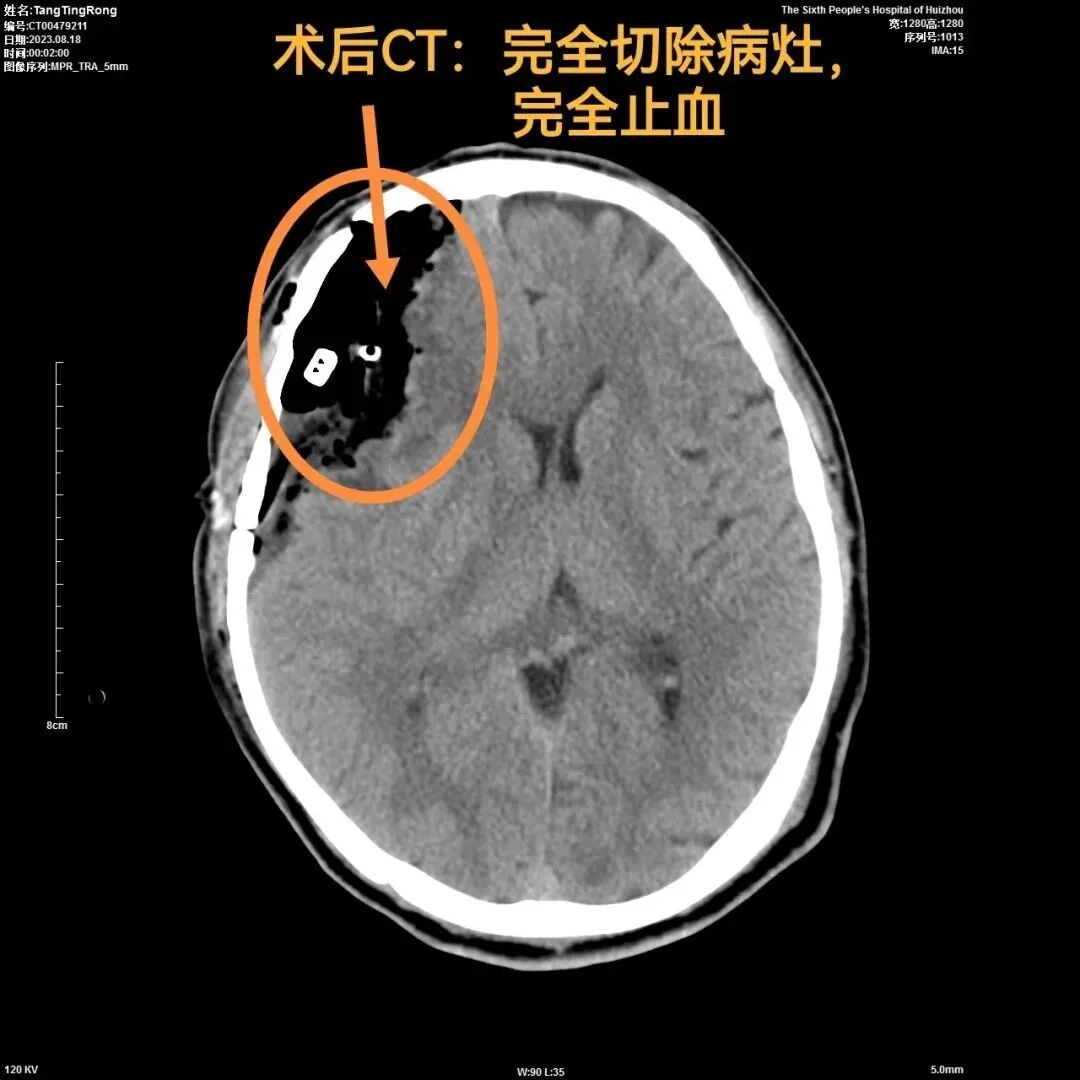

術後(hòu)第1天,病人完全蘇醒,完全對(duì)答切題,四肢活動自如,向(xiàng)醫生豎起(qǐ)兩(liǎng)隻大拇指點贊!術後(hòu)複查,病竈完全切除,完全止血。無任何後(hòu)遺症。